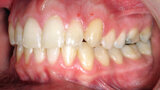

ClearCorrect treatment of crowding